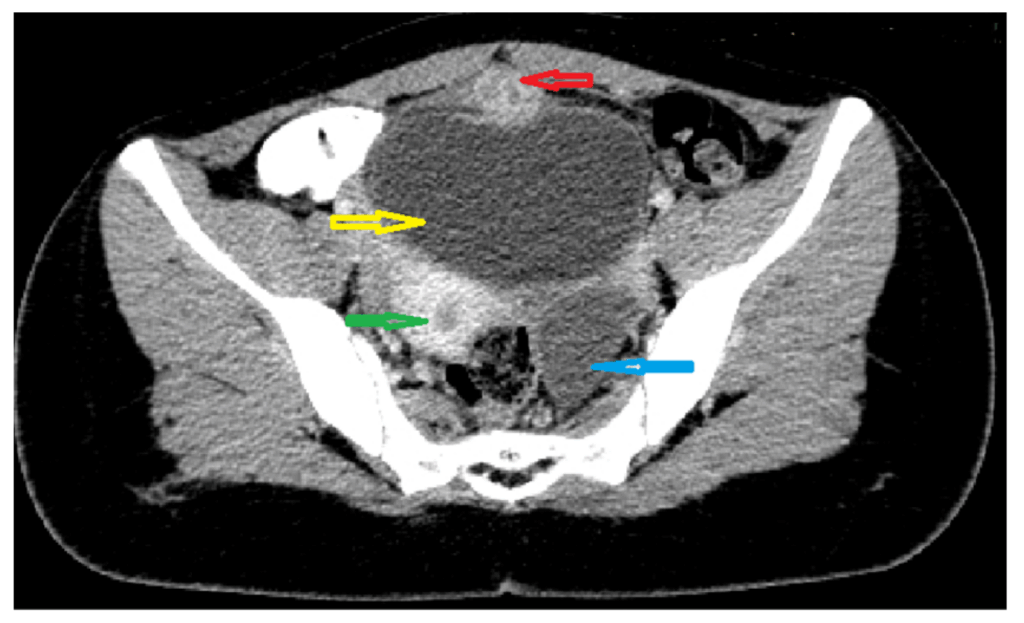

Upon presentation to a medical facility, diagnostic steps typically include a pelvic exam and ultrasound to confirm the rupture and assess any associated bleeding. In certain cases, a CT scan may also be utilized to gain a more detailed view of the abdominal cavity. For postmenopausal patients, a CA-125 blood test might be conducted to rule out potential malignancy, given that symptoms can sometimes overlap.

Specifically, when an ovarian cyst grows larger than 5 cm, its increased size can begin to press against sensitive pelvic nerves or the bladder. This persistent pressure often manifests as a dull, aching pain in the lower back. This referred pain is a crucial indicator that a cyst may be growing to a size that requires medical attention.

One primary factor is the cyst’s sheer size and the pressure it exerts on surrounding structures. When cysts grow larger than 10 cm, their increased mass can begin to compress nearby organs and tissues, including sensitive pelvic nerves like the sciatic nerves or the ureters. This persistent compression often results in pain that radiates into the lower back, potentially becoming chronic and debilitating.

This significant pressure can also lead to secondary complications, such as urinary retention if the bladder is heavily compressed, or chronic constipation if the intestines are affected. Monitoring symptoms like persistent pelvic fullness or bloating can help identify problematic cysts early. Early detection through advanced imaging techniques, such as MRI, is often crucial in preventing these more severe, long-term issues.